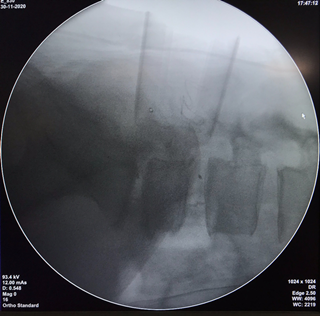

手术中可扩张通道辅助系统显示范围及减压固定的X片